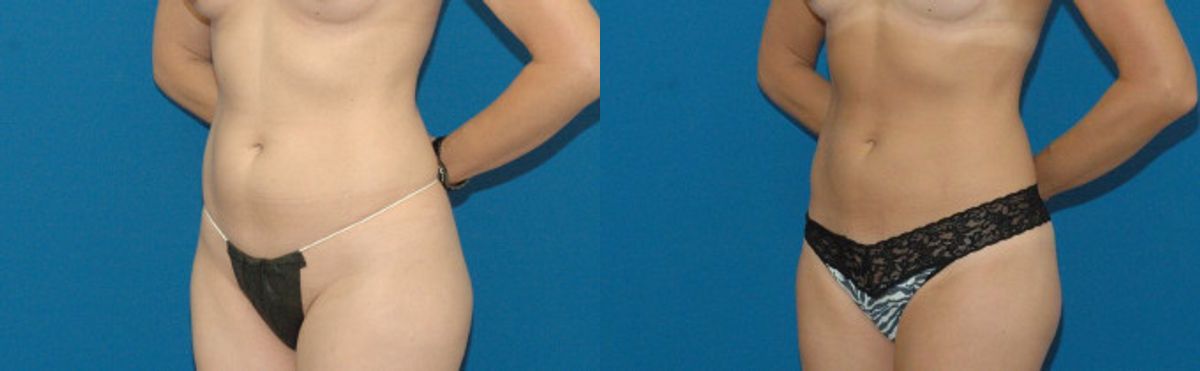

This patient desired improvement in the mild fattiness that she had along the abdomen and waist regions. She is an excellent liposuction candidate because of her youthful and elastic skin quality. She was treated with tumescent liposuction to the upper and lower abdomen, waist and hips. Her post operative result is depicted at one year after surgery, when all of the post operative swelling common with liposuction has resolved. Her cosmetic result is smooth and uniform with good improvement in the treated regions.